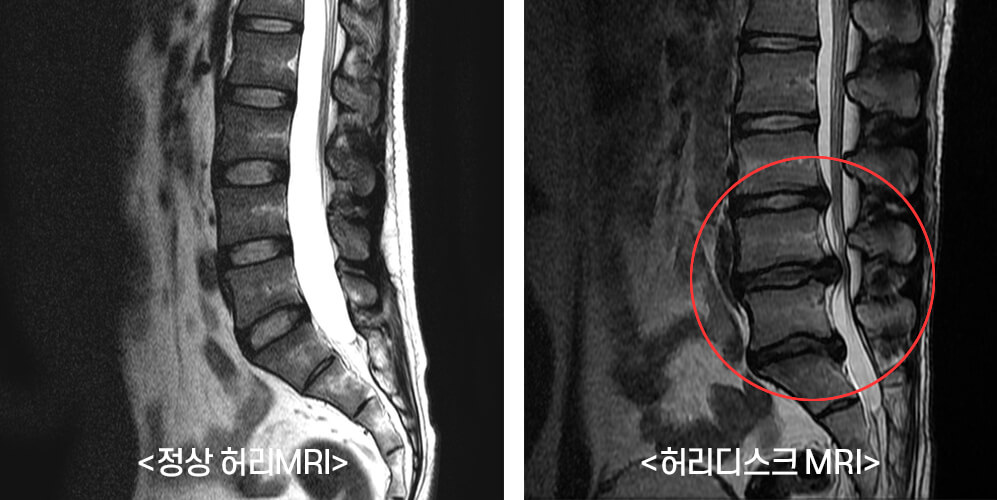

디스크는 외부로부터 물리적 충격을 이완시켜주며 딱딱한 뼈끼리 직접 부딪히는 허리디스크증상을 예방해요. 이런 디스크가 튀어나오면 염증이 생기고 신경을 누르기 시작해서 통증을 비롯한 갖가지 불편함이 나타나게 되어요. 원인은 바로 오랫동안 취하는 나쁜 자세라고 할 수 있다고 해요. 그뿐 아니라 무거운 물건을 갑자기 드는 행동과 허리에 무리가 가는 행동을 할 때에도 원인들로 꼽히고 있다고 합니다. 잘못된 자세를 지속할 경우에는 더욱 가중된 통증을 야기할 수 있다고 해요.

원래는 허리디스크 증상이 발병하게 되는 원인은 노화로 인한 퇴행성 변화가 주된 원인이었어요. 하지만 앞서 설명했듯 좌식생활이 일상화와 일반적인 때 잘못된 습관, 잘못된 자세를 지속해서 취하게 된다면 추간판 한쪽이 심하게 눌리게 되면서, 부담을 주게 되어 디스크로 이어지게 되는 것입니다. 일반적인 때 생활습관이 개선되지 않는다면 디스크를 치료하였다 할지라도 얼마 지나지 않아 다시 증세를 재발하게 생성하는 원인으로 이어질 수 있어 주의하셔야 합니다.